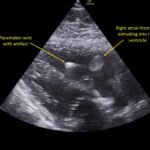

A 78-year-old gentleman presented to the emergency department (ED) for palpitations and dizziness. He had a complicated medical history including atrial fibrillation (AF), recently status post a Watchman procedure, oxygen-dependent chronic obstructive pulmonary disease (COPD), and heart failure with preserved ejection fraction (HFpEF). Point-of-care ultrasound (POCUS) revealed the presence of an intracardiac right atrial thrombus. Computed tomography (CT) angiography confirmed the presence of multiple pulmonary emboli (PE), and extension of the thrombus into the inferior vena cava. Pulmonary emboli are a common complication of thrombus in the right atrium. Management may include anticoagulation, thrombolysis, or thrombectomy. This case highlights that emergency physicians can expedite the diagnosis of intracardiac thrombus by using POCUS. The case presented describes a medically complex patient presenting with symptomatic right intracardiac and inferior vena caval thrombosis complicated by multiple PE. Point-of care ultrasound of the heart and lungs were included in his initial assessment, revealing findings of an intracardiac thrombus, and ruling out multiple other differential diagnoses including pericardial tamponade, pleural effusion, pulmonary edema, and pneumothorax. This finding changed the trajectory of this patient’s evaluation and management, and demonstrates the important role of POCUS in the care of ED patients with undifferentiated cardiopulmonary symptoms.